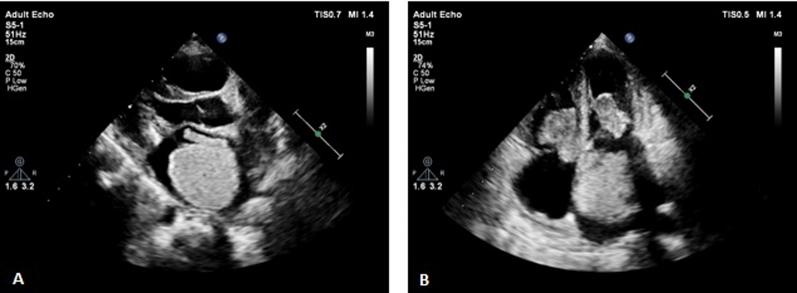

• Cardiac myxoma can present with prolonged fever and pleural effusion. • Multichamber myxoma should raise the suspicion of Carney complex. • Echocardiography plays a pivotal role for diagnosis, treatment planning, and follow-up. • Compatible with almost normal life expectancy if diagnosed, treated, and monitored. • Postsurgery recurrence of cardiac myxoma is common, demanding lifelong follow-up.

• 心脏黏液瘤可表现为长期发热和胸腔积液。

• 多腔黏液瘤应引起对卡尼综合征的怀疑。

• 超声心动图在诊断、治疗计划制定和随访中起关键作用。